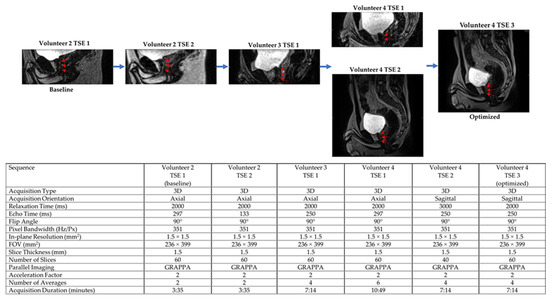

Both 3D HASTE and 3D TSE were qualitatively optimized for urethra visualization on low-field MRgRT using four healthy male volunteers. Echo time (TE), relaxation time (TR), and voxel size were tuned to provide urethra contrast while maintaining sufficient SNR. Additionally, the number of averages was tuned to increase image SNR and minimize motion/ghosting artifacts, while maintaining acceptable scan times. Figure 1 and Figure 2 show the MRgRT 3D HASTE and MRgRT 3D TSE optimization. Optimization steps for MRgRT 3D HASTE and TSE were similar. Volunteer 1 HASTE 1 and Volunteer 2 TSE 1 (baseline) show a noisy urethra with some urethral contrast. By increasing the number of averages to 6 and 4, the scan SNR improved and the final scan time was increased to 8:06 min and 7:14 min, respectively. Increasing TE to 407 ms (Volunteer 2 HASTE 1) resulted in lower SNR, but greater urethral contrast as T2-weighting increased. Conversely, decreasing TE to 135/133 ms (Volunteer 2 HASTE 2/Volunteer 2 TSE 2), resulted in higher SNR, but less urethral contrast as T2-weighting decreased. Increasing TR to 3000 ms (Volunteer 4 TSE 2) slightly improved SNR, but lowered urethral contrast, as prostate and urethral signal intensity were able to fully recover. Ultimately, TE of 246/250 ms and TR of 1800/2000 ms for MRgRT 3D HASTE/TSE was selected to provide adequate SNR and urethral contrast. Lower resolution (Volunteer 2 HASTE 2 and 3) of 2.0 mm isotropic, compared to 1.5 mm isotropic, provided higher SNR; however, 1.5 mm isotropic was selected to capture the prostatic urethra’s fine structure. Lastly, sagittal acquisition was preferred over axial acquisition for easier urethra visualization and delineation.

Figure 2. MRgRT 3D TSE optimization scheme using healthy male volunteers (red arrows pointing towards prostatic urethra).